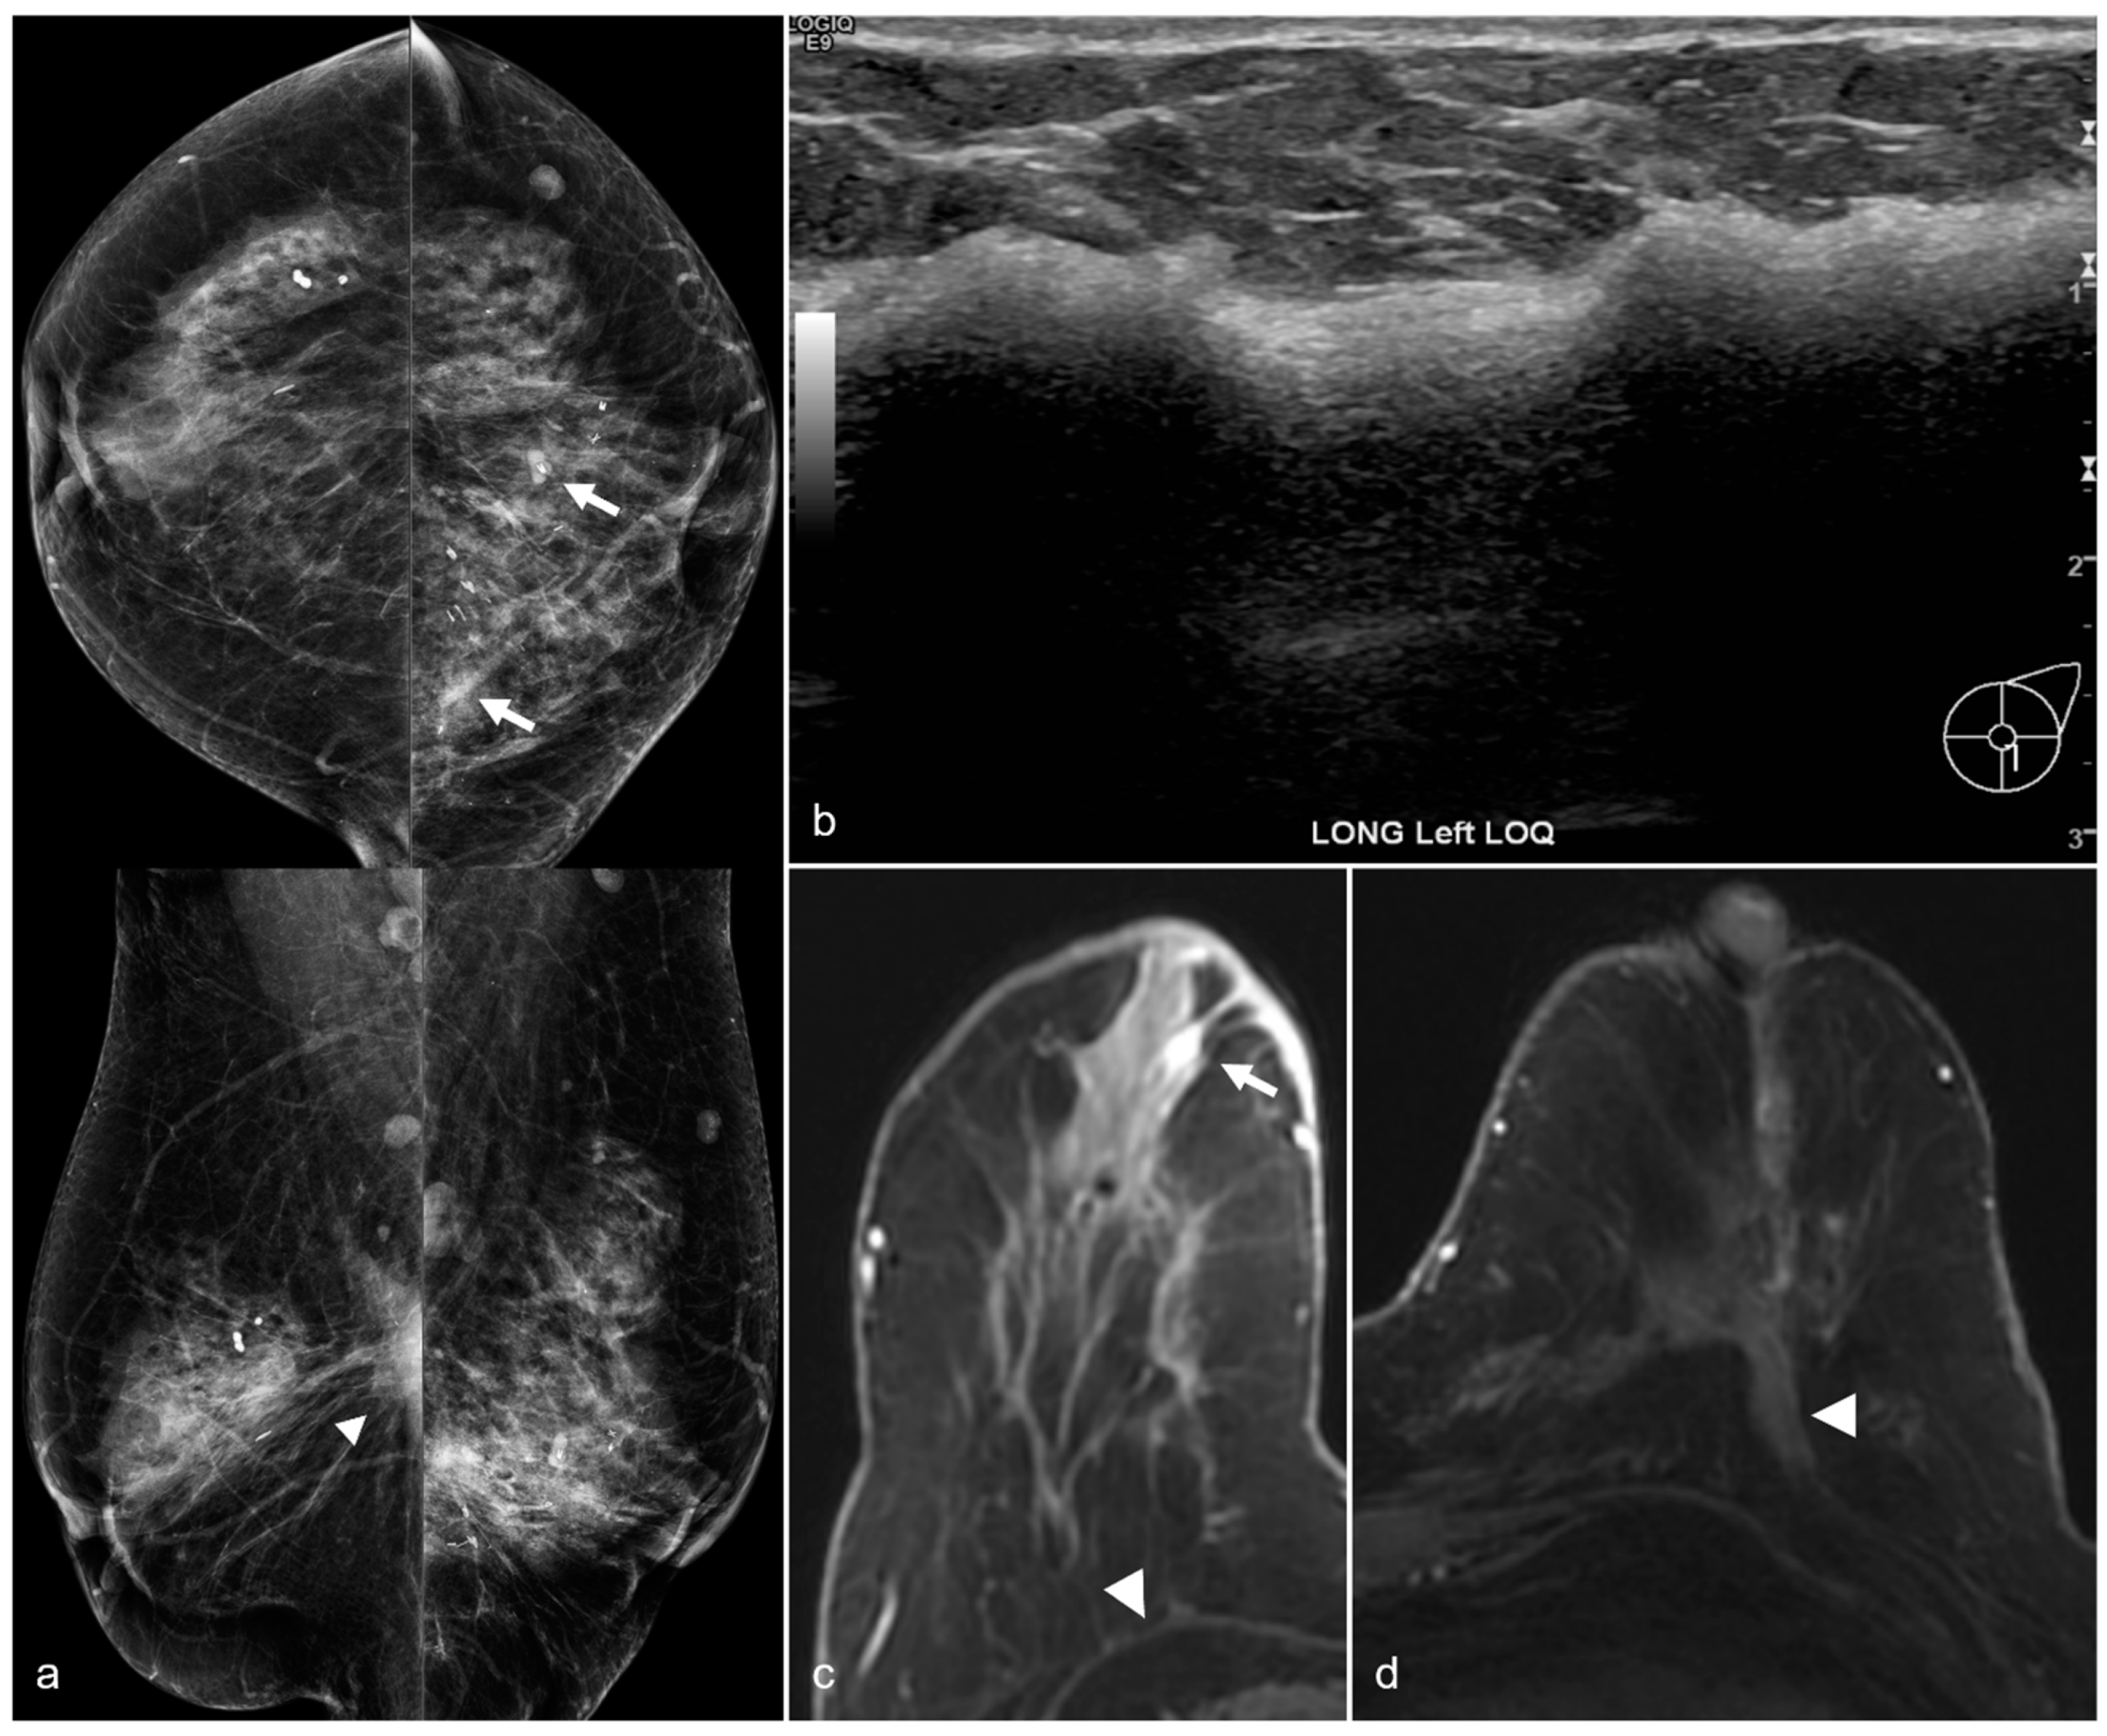

Figure 8. A 67-year-old woman with subglandular silicone implants developed a large, dense right subglandular mass (arrow) on mammography (a) two years after BES. Follow-up longitudinal right breast ultrasound (b) demonstrates a fluid collection with internal debris, confirming evidence of a seroma.

Figure 9. A 64-year-old woman status post BES due to silicone implant rupture. Spiculated masses (arrowheads) are seen in the pre-pectoral region on bilateral CC (a) and MLO (b) views. Hyperdense material (arrows) in both surgical beds and the bilateral axillae are sequelae of prior silicone implant rupture.